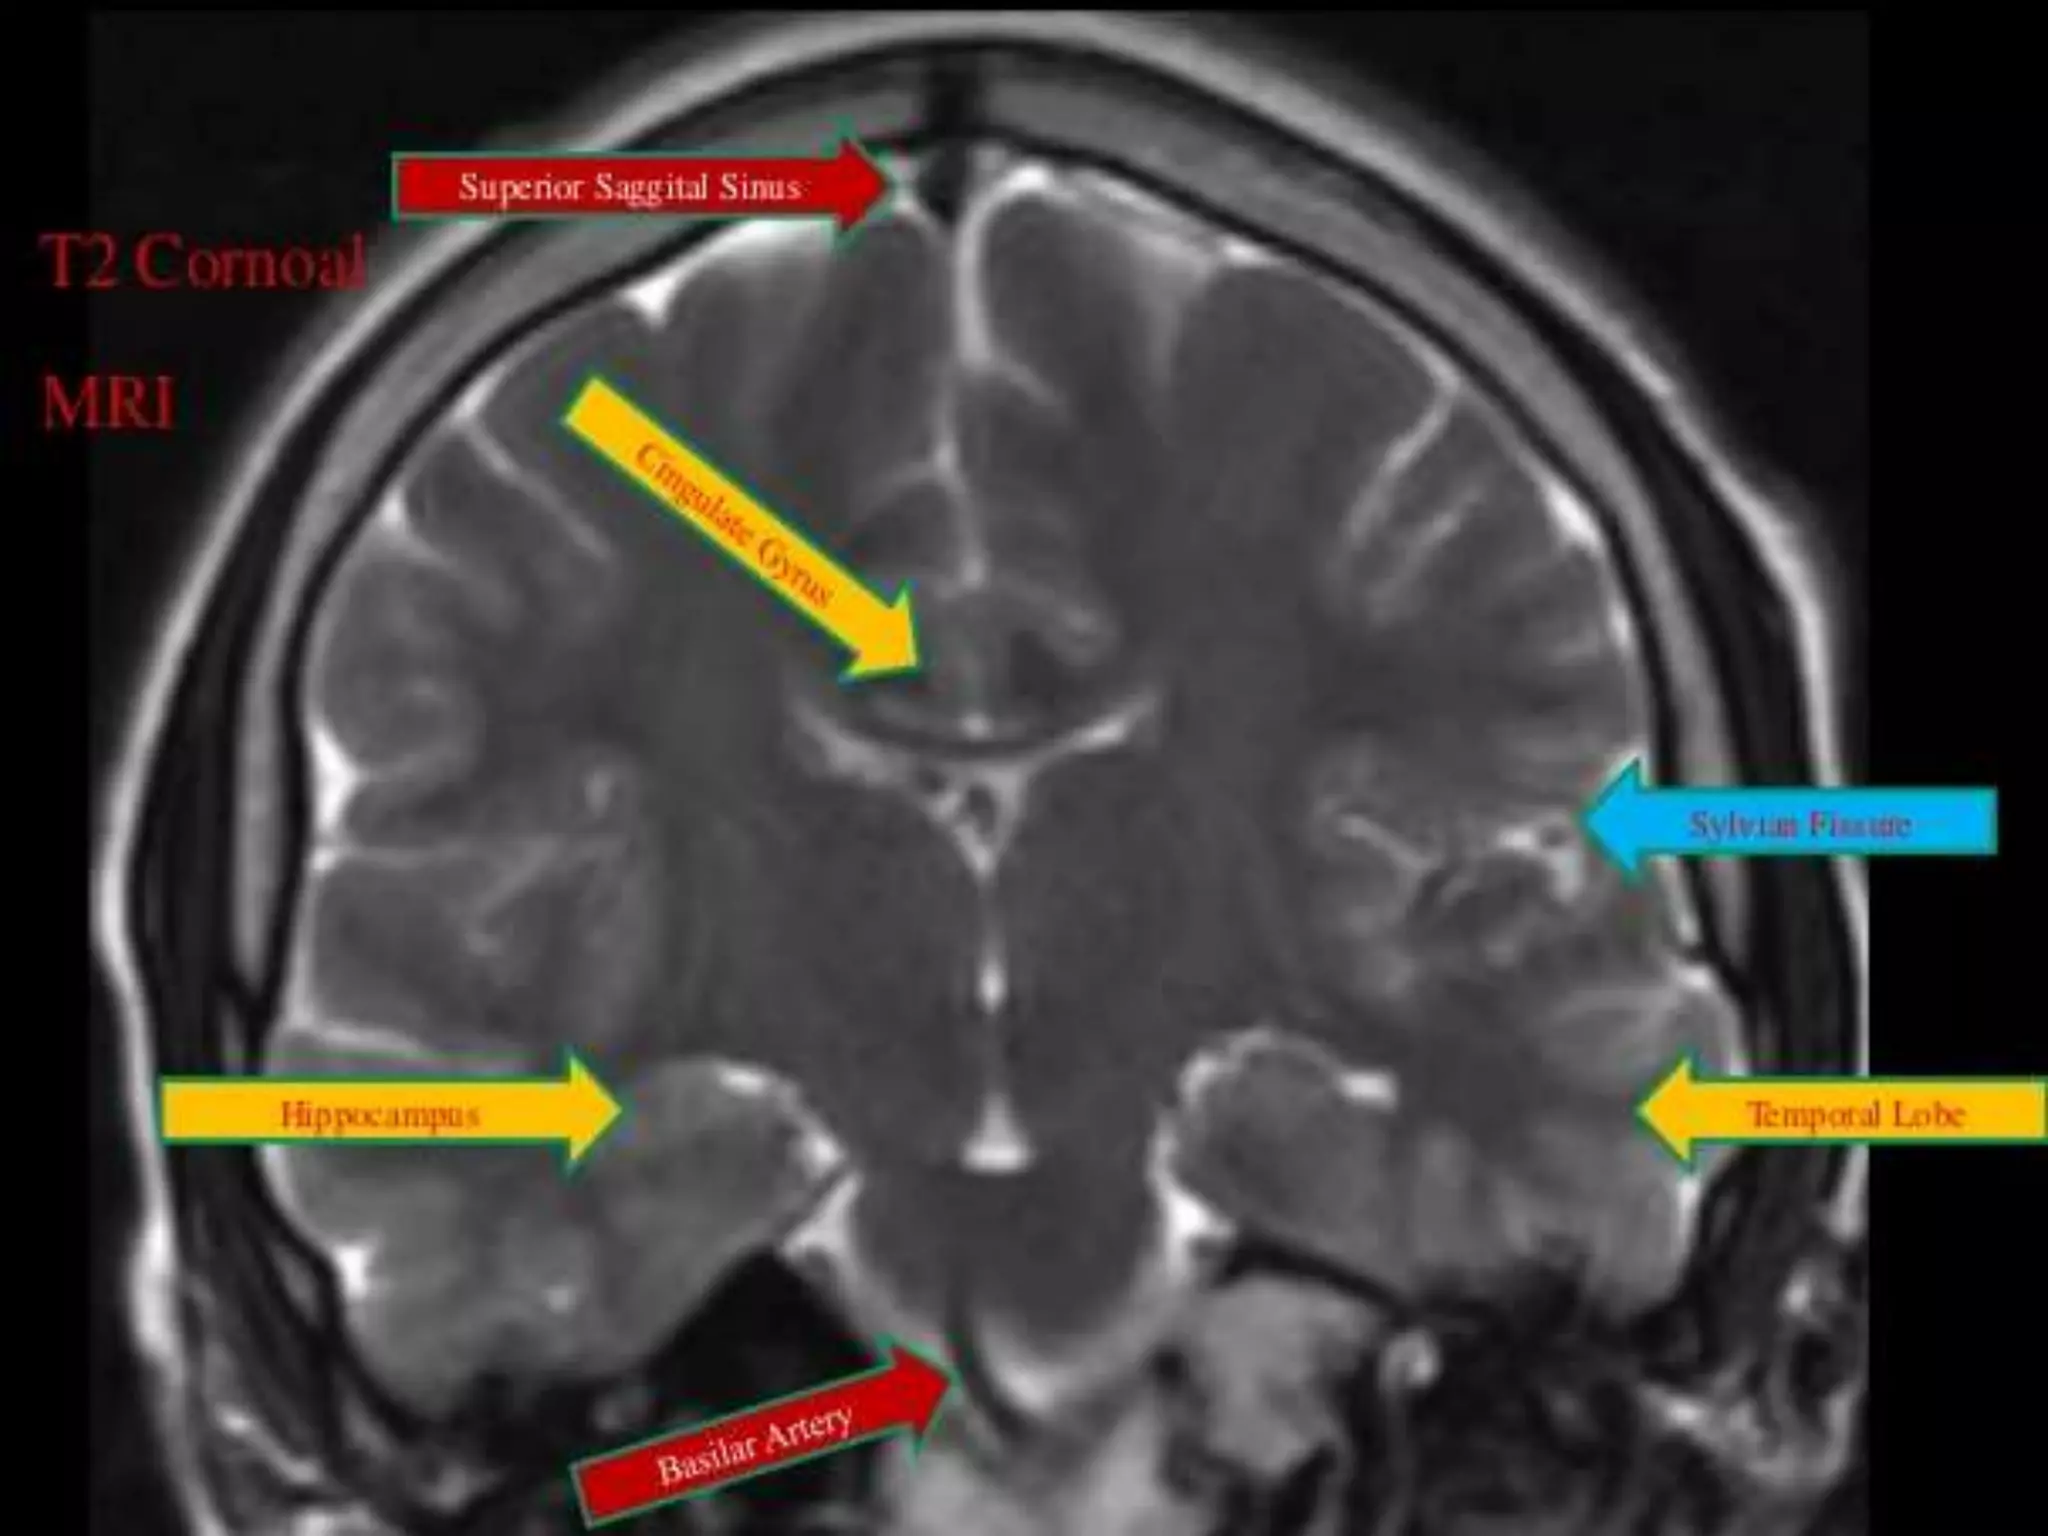

The two cerebral hemispheres are separated by

interhemispheric fissures and falx cerebri. On the lateral surface of the

brain, the sylvian fissure (lateral fissure) and the rolandic fissure (central

fissure) separate the cerebral hemisphere into the frontal lobe, temporal

lobe, parietal lobe, and a line drawn from the parieto-occipital sulcus

onto the preoccipital notch, delineating the boundaries of the parietal

and temporal lobes from that of the occipital lobe.

The brain derives its vascular supply via two carotid and two

vertebral arteries. The internal carotid artery bifurcates terminally into

the anterior and middle cerebral arteries. The two vertebral arteries

unite at the caudal border of the pons to form the basilar artery.